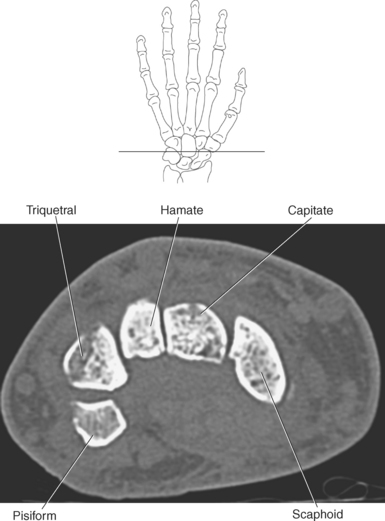

The bony anatomy of the wrist and hand consists of the distal radius and ulna, 8 carpal bones, 5 metacarpals, and 14 phalanges (Figure 9.101). Both the distal radius and ulna have a conical styloid process that acts as an attachment site for ligaments. The radial styloid process is located on the lateral surface of the radius, whereas the ulnar styloid process is located on the posteromedial side of the ulna. The carpal bones are arranged in proximal and distal rows. Located in the proximal row of carpal bones are the scaphoid (navicular), lunate (semilunar), triquetral (triquetrum), and pisiform bones. The pisiform is considered a sesamoid bone that is embedded in the tendon of the flexor carpi ulnaris. The distal row consists of the trapezium (greater multangular), trapezoid (lesser multangular), capitate (os magnum), and hamate (unciform) bones (Figures 9.102 through 9.114). The five metacarpals are small tubular bones with a proximal end (base), distal end (head), and shaft (body). The 14 phalanges that make up the fingers are short tubular bones. Like the metacarpals, each phalanx consists of a proximal (base), middle (body or diaphysis), and distal (head) portion. Each digit consists of 3 phalanges (proximal, middle, and distal), except for the thumb (first digit), which has only 2 phalanges (proximal and distal). The articulation of the phalanges of the second through fifth digits creates three interphalangeal joints: the metacarpophalangeal (MCP) joints classified as condyloid joints, proximal interphalangeal (PIP), and distal interphalangeal (DIP). The proximal and distal interphalangeal joints are classified as hinge joints (Figure 9.101). The first digit, which consists of 2 phalanges, has just two joints: the MCP joint, classified as a saddle joint, and an interphalangeal joint, classified as a hinge joint (Figure 9.101).